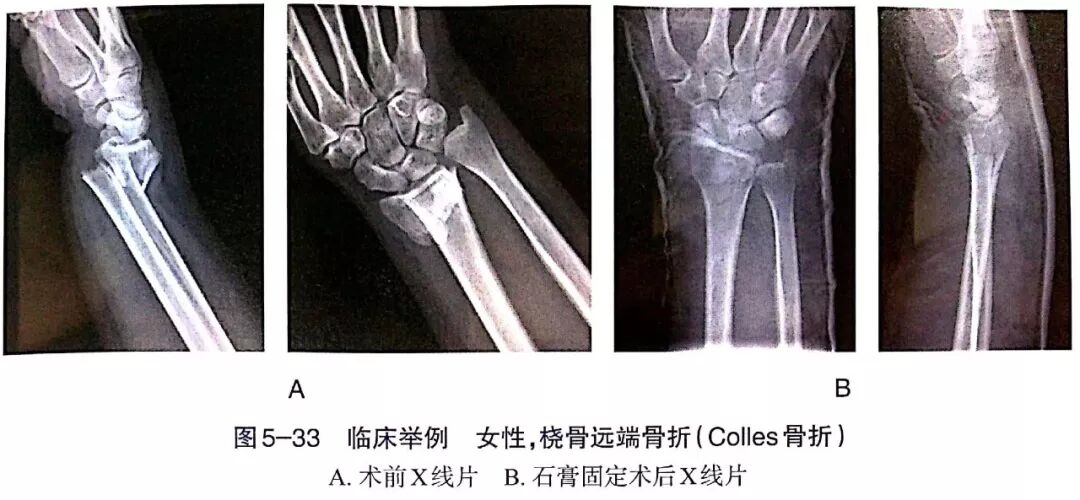

- Distal Radius Fractures: Fracture patterns (Colles, Smith, Barton) are influenced by the mechanism of injury (FOOSH with wrist in extension vs. flexion) and muscle forces (brachioradialis, pronator quadratus, intrinsic hand muscles). Understanding the deforming forces helps predict displacement (e.g., dorsal displacement in Colles) and guides reduction.

- Ulnar deviation and pronation (for Colles type).

- Immobilization: Short arm cast or sugar-tong splint, often with the wrist in slight flexion and ulnar deviation.

- Acceptable Parameters: Guidelines (e.g., from AAOS) suggest acceptable radiographic parameters for non-operative management typically include <2-3 mm radial shortening, <2 mm articular step-off, and dorsal tilt <10-20°. However, these are often modified by patient age and functional requirements.

Clinical and Radiographic Imaging